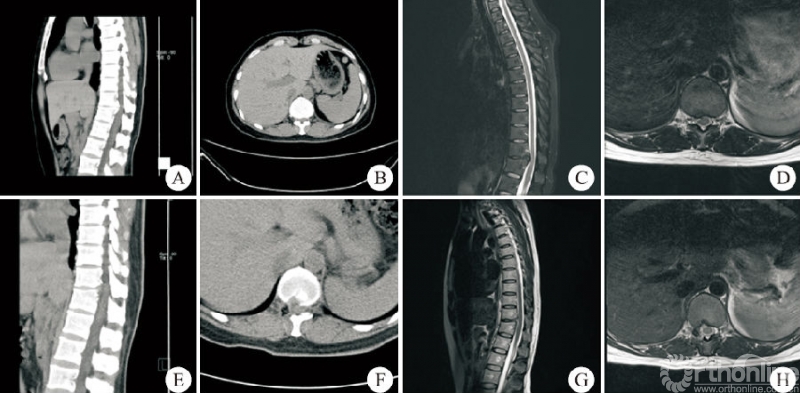

所有患者的手术由同一位术者完成,手术均顺利完成,无硬膜外血肿、切口感染及术后瘫痪者。37例患者中男14例,女23例;年龄31~82岁,平均(57.6±11.8)岁。上胸段(T1−T4)1例,中胸段(T5−T9)7例,下胸段(T10−T12)29例。24例采用俯卧位,13例采用侧卧位。平均住院时间(7.2±1.6)d,平均手术时长(96.5±20.0)min。平均出血量(41.9±10.8)mL。24例俯卧位手术患者均为OLF,做“漂浮”处理的3例,2例患者术中硬膜破裂(图3)。13例侧卧位手术患者中TDH3例,OPLL5例,OLF+OPLL5例,做“漂浮”处理的1例,2例患者术中硬膜破裂(图4)。术后影像学检查示椎管减压充分,致压物被完全去除。

女,38岁,T11−T12后纵韧带骨化,行侧卧位经皮内镜可视化环锯椎管减压术。A、B:术前CT矢状位和横断位示T11−T12鸟嘴型后纵韧带钙化;C、D:术前MRI示脊髓腹侧严重受压;E、F:术后CT矢状位和横断位示钙化的后纵韧带完全去除单侧关节突关节成形;G、H:术后MRI示脊髓腹侧致压物完全去除硬膜充分膨胀。图4 T11−T12侧卧位胸椎后入路术前与术后影像学资料